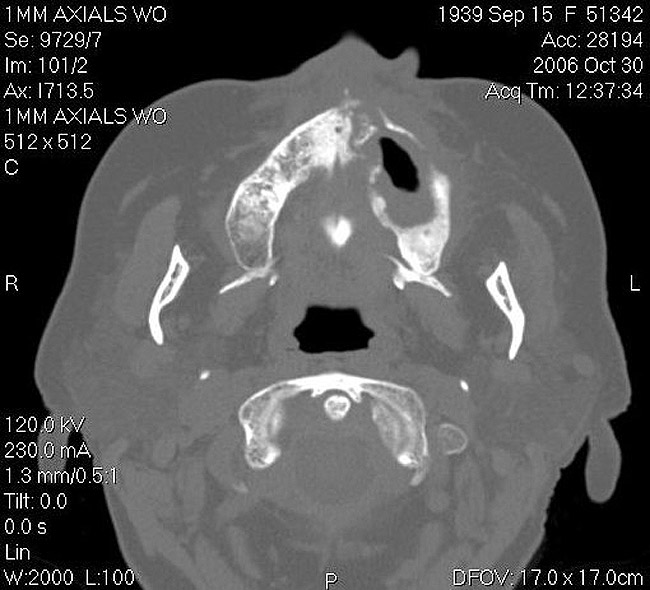

As stated earlier, spontaneous osteonecrosis is also possible. Figure 14 shows a case of spontaneous BRONJ resulting from wearing an ill-fitting denture. The patient had noticed the foreign material, but chose not to act on it. When the material was removed in the dental office (Figure 15 and Figure 16), blood streamed from the nose so severely that the patient had to be sent to an ear, nose, and throat (ENT) physician. The ENT took a computed tomography scan, which showed a large radiolucency in the upper left quadrant where the foreign material once had been (Figure 17). A review of the radiograph (Figure 18) showed that bone in the maxillary arch had decreased mineral density compared with the mandible. The biopsy report found necrotic bone with organisms consistent with actinomyces. These findings were consistent with biopsies found in the literature.22 When the patient returned for a 1-week follow-up, she still had signs of infection and the site had a foul odor and a discharge (Figure 19). The patient was informed that she should follow up with the ENT and return to the dental office after the infection had been resolved.

Figure 17  CT scan showing extensive bone loss.

Figure 17